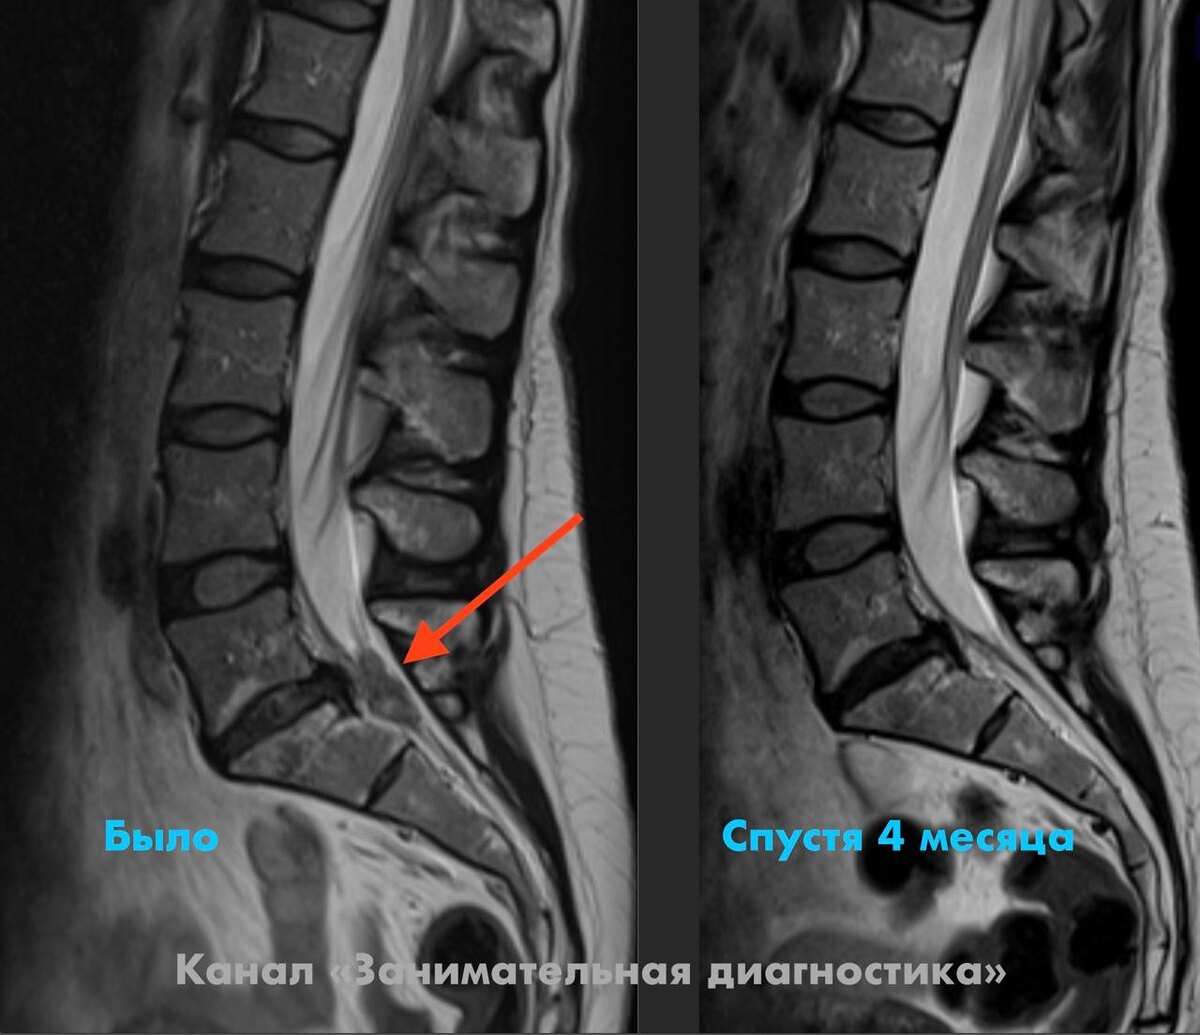

Пациентка очень обрадовалась и решила пока не делать операцию — до этого один врач настаивал на хирургическом вмешательстве, второй советовал подождать, и она не знала, как поступить.

Спустя 4 месяца на контрольном МРТ ожидания оправдались: грыжевой секвестр уменьшился в несколько раз, самочувствие пациентки заметно улучшилось, а «прострелы» по ноге ушли.

Тема спонтанной резорбции грыж диска — это тот случай, когда природа иногда работает лучше нейрохирурга. Но давайте без мистики — только цифры и факты. 😎